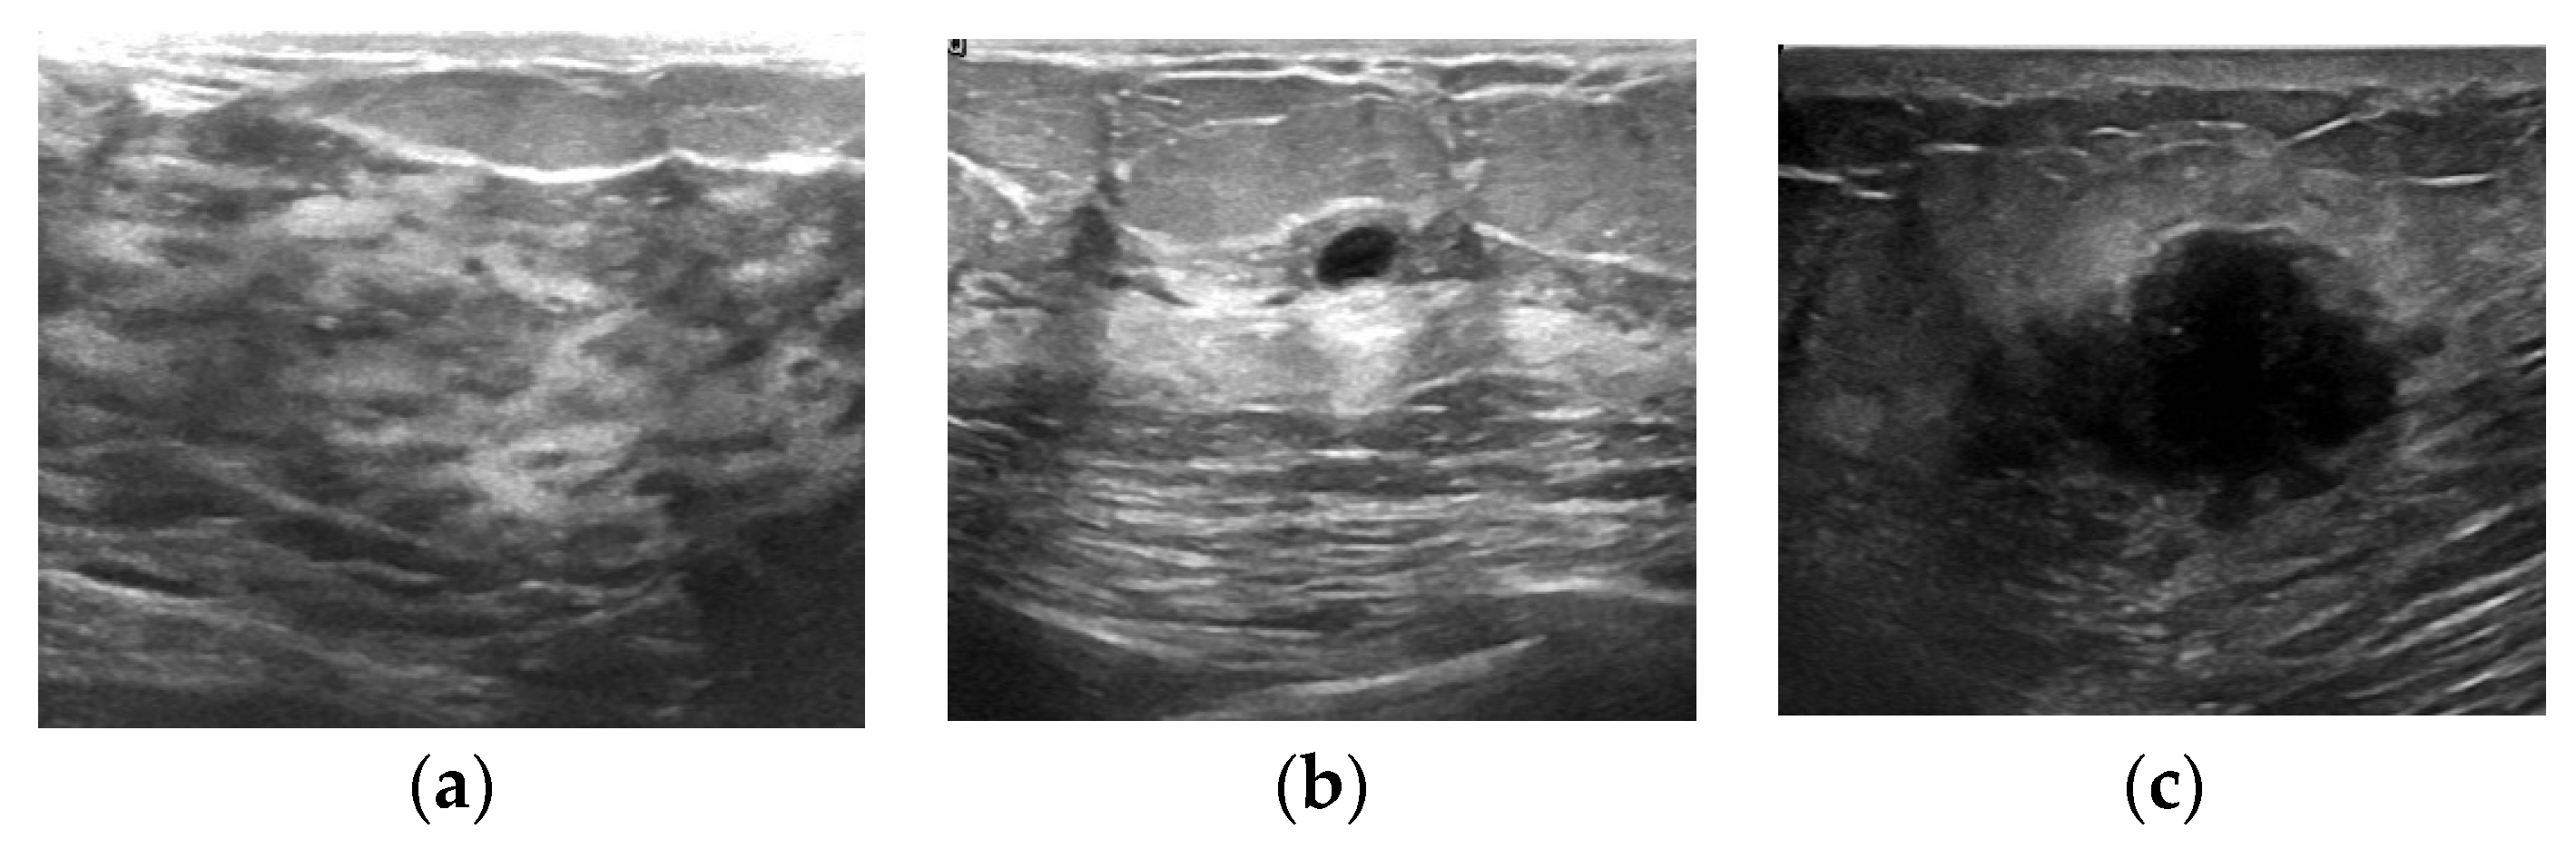

The three types of images in the dataset are shown in Figure 7. Figure 7a is a normal image, Figure 7b is a benign tumor image, and Figure 7c is a malignant tumor image. The number of images in each category is shown in Table 2. As shown in Table 2, the dataset contains 133 normal images, 437 benign images, and 210 malignant images. Since the experiment does not involve normal instances, we increase the number of malignant instances and realize data expansion by rotating the malignant image 90 degrees. Finally, 420 malignant images are obtained.

Figure 7. Three types of images in the dataset of breast ultrasound images. (a) Normal; (b) benign; (c) malignant.

The dataset of breast ultrasound images is categorized into three classes, i.e., normal, benign, and malignant, as shown in Figure 7. In our work, the dataset combines normal and benign into negative and classifies malignant as positive.